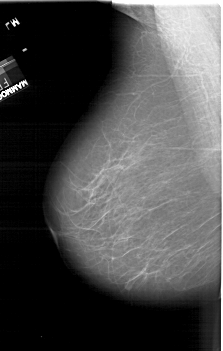

ics_version 1.0 filename A-1494-1 DATE_OF_STUDY 7 2 1994 PATIENT_AGE 61 FILM FILM_TYPE REGULAR DENSITY 2 DATE_DIGITIZED 25 8 1998 DIGITIZER HOWTEK 43.5 SEQUENCE LEFT_CC LINES 6871 PIXELS_PER_LINE 4141 BITS_PER_PIXEL 12 RESOLUTION 43.5 NON_OVERLAY LEFT_MLO LINES 6316 PIXELS_PER_LINE 4006 BITS_PER_PIXEL 12 RESOLUTION 43.5 NON_OVERLAY RIGHT_CC LINES 6436 PIXELS_PER_LINE 4126 BITS_PER_PIXEL 12 RESOLUTION 43.5 OVERLAY RIGHT_MLO LINES 6616 PIXELS_PER_LINE 4126 BITS_PER_PIXEL 12 RESOLUTION 43.5 OVERLAY |